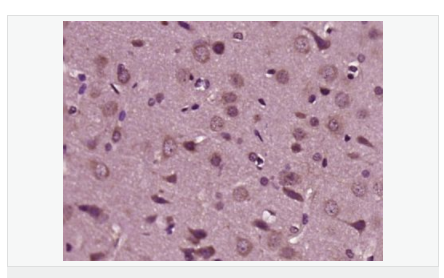

| 产品应用 | WB=1:500-2000 ELISA=1:5000-10000 IHC-P=1:100-500 IHC-F=1:100-500 ICC=1:100-500 IF=1:200-800 (石蜡切片需做抗原修复) not yet tested in other applications. optimal dilutions/concentrations should be determined by the end user. |